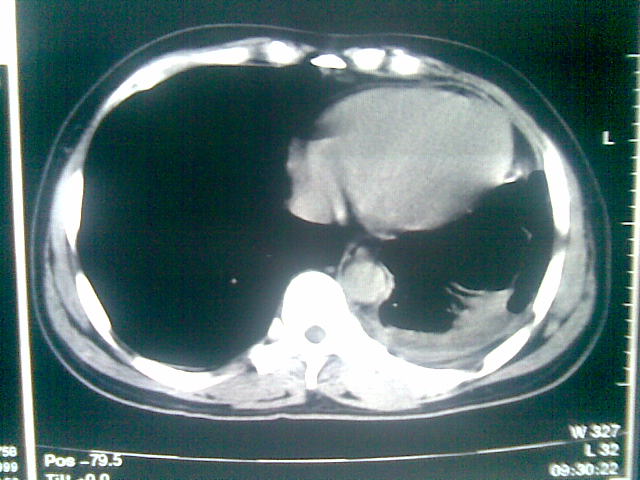

标题: CT23981:男,38岁阑尾炎术后透视胸腔积夜!做CT如下!积液包 [打印本页]

标题: CT23981:男,38岁阑尾炎术后透视胸腔积夜!做CT如下!积液包

可能与阑尾术后关系不太大,1.胸膜增厚粘连见少量气体。包裹脓气胸?左侧网膜囊脓肿?

.胸膜增厚粘连见少量气体。包裹脓气胸

左侧胸膜增厚、粘连+包裹液气胸。